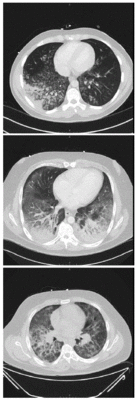

| Изображения компьютерной томографии, показывающие диффузные инфильтраты в лёгких у трех пациентов, 2019 год | |

Компьютерная томография больных зафиксировала лёгочный инфильтрат: диффузные или располагающиеся в нижних отделах уплотнения по типу «матового стекла» с сохранением структуры в субплевральных (78,1 %), лобулярных (59,4 %) или перибронховаскулярных (40 %) областях. Последнее встречалось у более молодых пациентов и не являлось характерным при остром повреждении лёгких[13][14]. При поступлении в больницу у всех пострадавших наблюдалось повышенное количество лейкоцитов с преобладанием нейтрофилов и отсутствием эозинофилии[12][4][15]. Плазма потребителей электронных сигарет также показывала повышенный уровень гидроксиэйкозатетраеновой кислоты и различных эйкозаноидов[6].